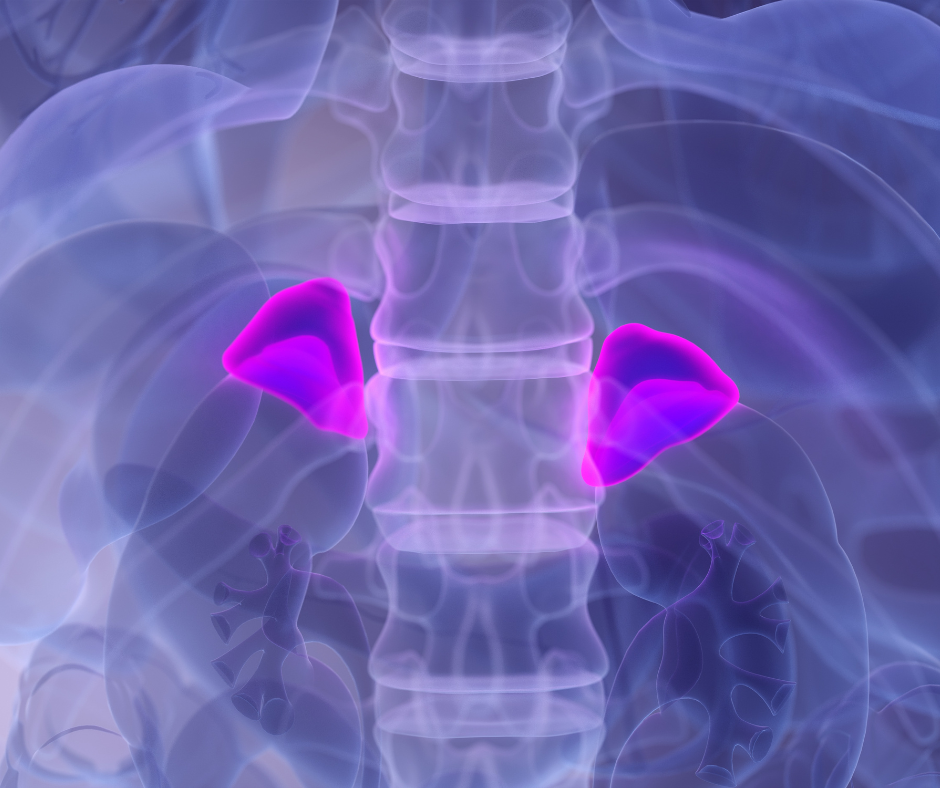

Kortizol, známy aj ako „stresový hormón“ má v tele mnoho dôležitých funkcií a neustále sa uvoľňuje v malých množstvách, aby udržiaval homeostázu (rovnováhu). Vylučuje ho kôra nadobličiek ako odpoveď na stresové situácie, ale má aj množstvo ďalších úloh, ktoré sú nevyhnutné pre správne fungovanie organizmu.

Produkcia kortizolu je riadená hypofýzou a hypotalamom, dvoma časťami mozgu, ktoré sú kľúčové pre reguláciu hormonálnej rovnováhy.

Hladiny kortizolu sa prirodzene menia počas dňa: Najvyššie sú ráno, čo pomáha telu sa „prebudiť“ a pripraviť sa na deň. Počas dňa hladina postupne klesá a je najnižšia večer, keď sa telo pripravuje na spánok.

Hoci je kortizol nevyhnutný pre prežitie, dlhodobo zvýšené hladiny môžu mať negatívny vplyv na zdravie. Ako znížiť hladinu kortizolu?